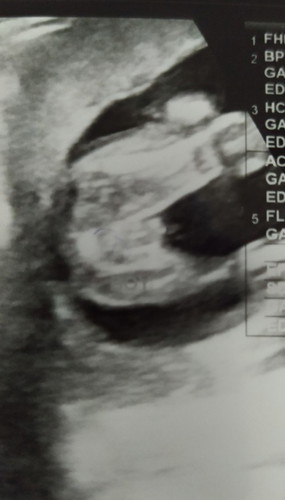

Dah beberapa hari sakit sgt dkt bawah perut. Kadang kiri kadang kanan sampai tahap tak boleh nak jalan, berdiri. Even pakai seluar pun sakit. Try la p scan risau ada cyst membesar ke apa. Alhamdulillah cyst dah takda. Semua okay. Mungkin faktor baby nak membesar. Dapatlah check jantina terus. Mula2 doc kata macam gegirl. Pehtu belek2 mcm boboi pun ada. So nanti kene scan lagi kalau nak puas hati. Ada tak ibu2 scan boboi mcm ni?#firstbaby #firstmom